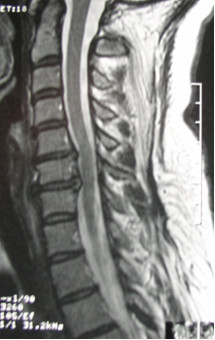

Obraz przedstawia: